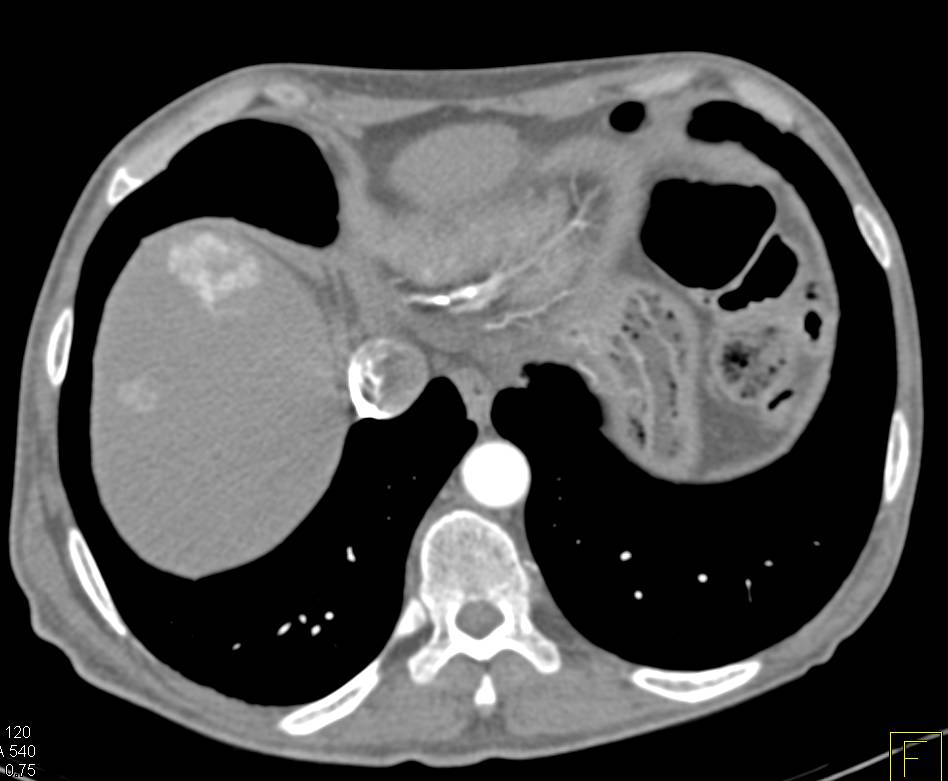

Central Intraductal Papillary Mucinous Neoplasm (IPMN) with a Carcinoma